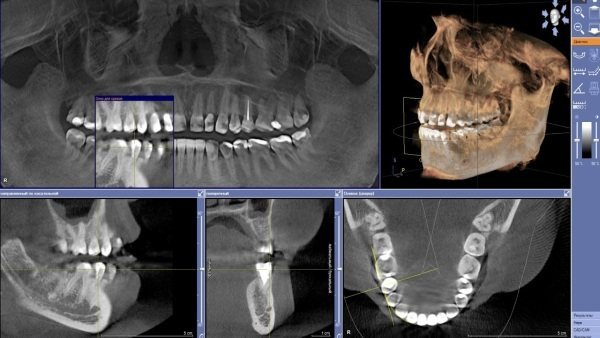

2. Обов’язково повинен бути зроблений панорамний знімок обох щелеп. В ідеалі такий рентген краще замінити на комп’ютерну томографію, яка дозволить визначити, наскільки зруйновані м’які тканини, що розташовуються біля зубів. Ця процедура дозволяє отримати тривимірні дані.Десна опускаються.  Що робити, якщо оголюються зуби, з'явилися жовті плями, що це таке, як їх відновити, лікування, причини